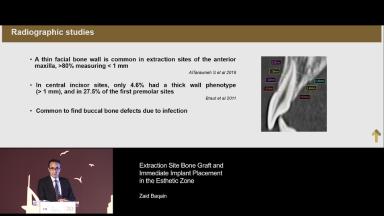

Patient expectations continue to increase, with the majority of patients expecting to have immediate replacement of missing teeth. This lecture provides a sound understanding of the key factors surrounding immediate implant placement. Advantages and disadvantages of this approach are discussed, using various cases to illustrate key points. Factors influencing esthetic outcome are discussed, with a good selection of evidence based information being presented.

describe the factors influencing success and failure of immediate implant placement

explain factors that influence esthetic outcome